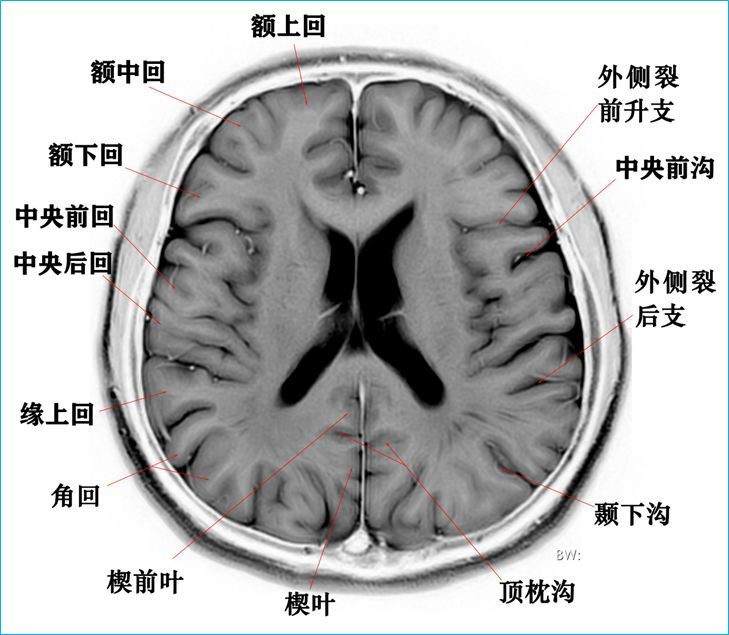

3.0t-t2wi反相图学颅脑断层解剖

图片尺寸729x635